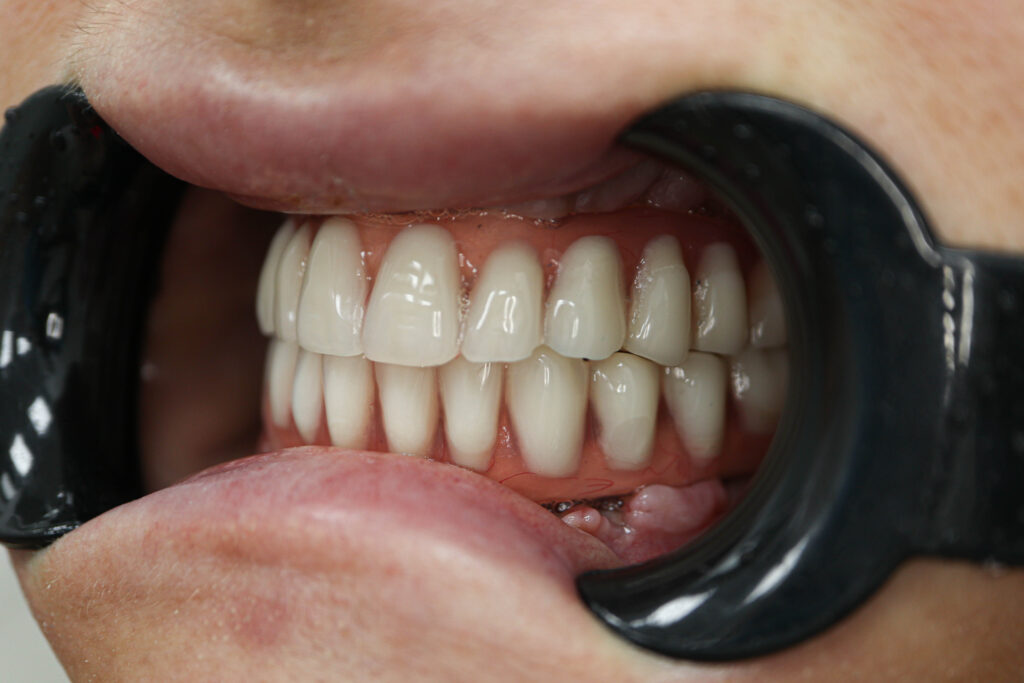

Результаты

Установка 6 классических имплантатов NeoDent и 3 скуловых имплантата